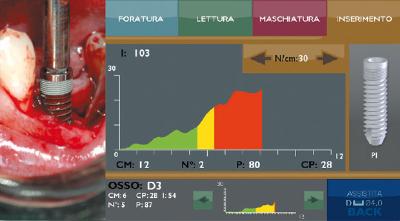

Motore chirurgico TMM2

L'unità per implantologia TMM2 IDi Evolution consente di individuare e quantificare il tipo e la consistenza dell'osso (densità ossea del sito implantare), scegliere l'impianto più adatto come forma e tipo di spire e infine di misurare la stabilità primaria (quanto l'impianto è correttamente "inglobato" nell'alveolo). Tutto quindi per avere meno rischio e risultati maggiormente prevedibili.